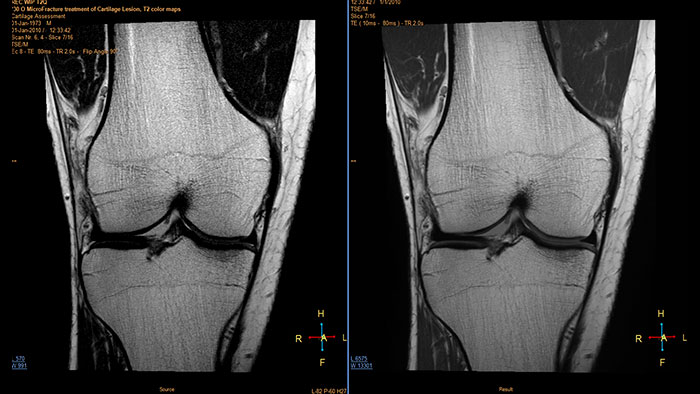

Visualize cartilage structures

Enables the visualization of cartilage structures integrated with color-coded T2 maps. Positioning of cartilage-shaped, layered region of interest is used to assess variation of T2 values across the cartilage depth to determine the degradation of the cartilage.